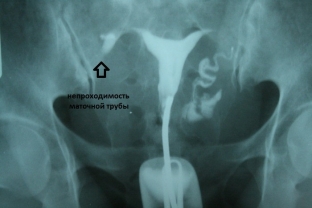

- hysterosalpingography is an X-ray contrast study that best visualizes adhesive processes in the pelvic organs;